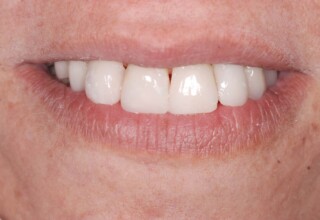

Porcelain Veneers

The best way to solve esthetic problems of the anterior teeth. They combine very little tooth grinding with very high esthetic performance. In the following extensive case anterior teeth presented with: old restorations, staining, poor shape, length and tooth –gingiva ratio. Meticulous diagnostic waxing was performed on study casts and temporary veneers were manufactured. Temporary veneers were used intraorally to evaluate the incorporated changes and to further modify and adjust were needed. When esthetics and function were approved by the patient and were satisfying for the operator the temporaries were used as a guide for the final porcelain veneers. The five final veneers on the upper anterior teeth restored the smile of the patient to almost perfection.

Initial appearance

Final appearance